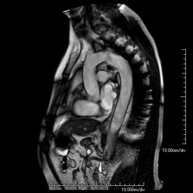

- Female pelvis MRI

This non-invasive diagnostic procedure uses an electromagnetic field and radio waves (from a transmitter and receiver) to acquire high-definition anatomical images of the pelvis. It is a radiation-free procedure. It is performed to study pathologies of the uterus, ovaries, fallopian tubes and vagina, whether they are of tumour, inflammatory or vascular origin. The procedure also enables the assessment of adjacent structures located in the pelvis, identifying any abnormalities. Sometimes intravenous contrast (gadolinium) is required to characterise the lesions.